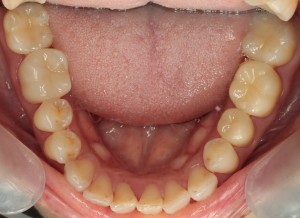

-

きれいな歯になりました!